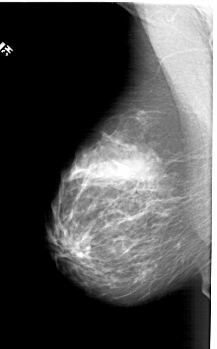

A_1394_1.LEFT_CC

LEFT_CC LINES 5731 PIXELS_PER_LINE 3481 BITS_PER_PIXEL 12 RESOLUTION 43.5 NON_OVERLAY